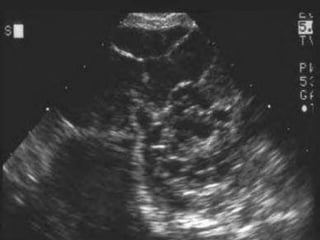

Imagenología

 Ecografía

 Tumores malignos: Multiloculados, sólidos ó ecogénicos,

mayores de 5cm, tabiques gruesos con áreas de

nodularidad.

 Flujometría doppler: Proyecciones papilares,

neovascularización.

 USG abdominal de difícil interpretación en pacientes

con enfermedad avanzada o masas tumorales grandes.

 Ascitis.

Imagenología  Ecografía  Tumoresmalignos: Multiloculados, sólidos ó ecogénicos, mayores de 5cm, tabiques gruesos con áreas de nodularidad.  Flujometría doppler: Proyecciones papilares, neovascularización.  USG abdominal de difícil interpretación en pacientes con enfermedad avanzada o masas tumorales grandes.  Ascitis. Schorge JO, Schaffer JI, Halvorson LM, Hoffman BL, Bradshaw KD, Cunningham G. “Cáncer ovárico epitelial”. En: Schorge JO, Schaffer JI, Halvorson LM, Hoffman BL, Bradshaw KD, Cunningham G. Williams de Ginecología. México: McGraw.-Hill; 2009. Pp. 716-737.